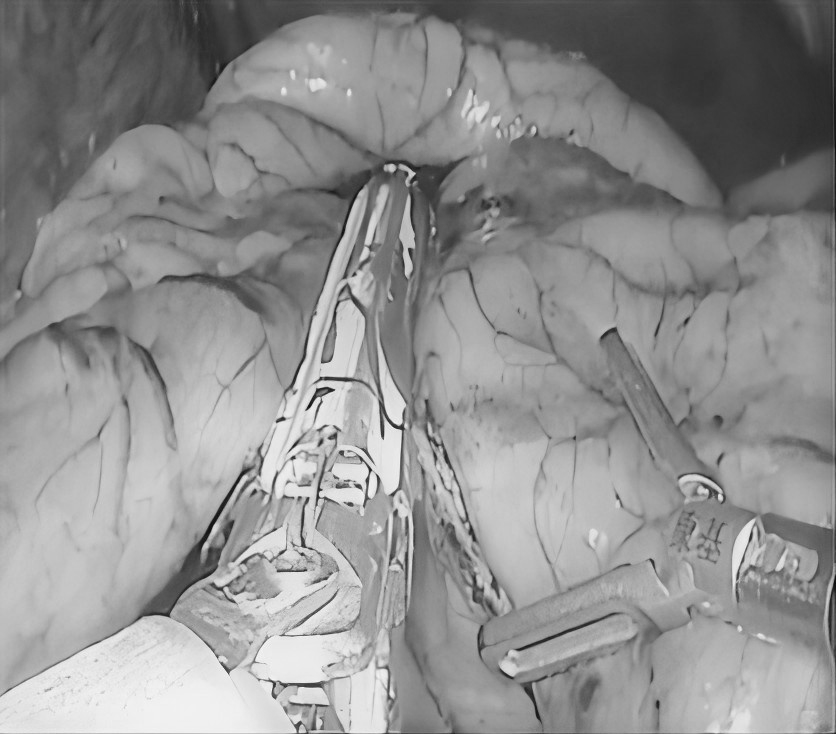

3月5日,贵州航天医院第51次晨读会由我院普外科主任、主任医师梁跃作学术交流,他以“腹腔镜下清扫No.253淋巴结的解剖问题”为题,全面讲解了No.253淋巴结的定义、清扫指征、清扫范围、相关解剖学知识等具体情况,并结合实际案例与图文对相关解剖进行了详细剖析,形象地展示了该区域复杂的解剖结构及在手术过程中可能遇到的解剖难点与要点。 普外科专家简介 梁 跃 普外科主任 主任医师 临床擅长:对普外科各类肿瘤手术具有丰富的临床经验。 毕业于遵义医学院,遵义市医学会小儿外科学分会常务委员,遵义市肛肠协会理事,遵义市医学会核医学分会(第二届)委员会委员;荣获第三期“黔医人才计划”优秀学员称号;主持市级课题1项,完成省级课题1项,在国内各类刊物上发表论文10余篇。 钱科洪 普外科 副主任医师 临床擅长:从事普外科临床工作30余年,对各类普外科疾病的诊治、乳腺、甲状腺、胃十二指肠、结直肠等疾病及疑难杂症具有丰富的临床诊疗经验。 毕业于遵义医学院临床医疗系,2009年前往中山大学附属第一医院微创外科进修学习,在国内各专业期刊发表论文数篇。 普外科简介 基本情况 贵州航天医院普外科成立于1968年,前身属于航天部O61基地3417医院外一科,3417医院、3427医院合并后更名为普外科,下设胃肠外科、肛肠外科2个亚专业科室,是中国疝病专科联盟单位,贵州医科大学附属医院胃肠外科专科联盟单位。开放床位40张,配备医护人员21人。 专科特色 普外科致力于胃肠及肛肠疾病的外科临床诊治及科研,以腹腔镜微创外科技术为本,形成以快速康复治疗胃肿瘤、结直肠肿瘤、小肠肿瘤、直肠脱垂、肥胖病、急腹症、各类疝、痔、瘘等专科特色,同时注重胃肠疾病尤其是结直肠恶性肿瘤的基础研究和临床转化研究,总体诊断和治疗水平在区域同级医院居于领先水平。 开展手术:腹腔镜下胃癌根治术,腹腔镜下袖状胃切除术,腹腔镜下胃肠道间质瘤切除术,腹腔镜下结、直肠癌根治术,胃癌、结直肠癌的精准治疗,腹腔镜下小儿疝气、成人疝修补术,腹腔镜下阑尾手术,内痔的硬化注射治疗及痔疮的微创治疗:ATH、PPH、TST,直肠脱垂的各种手术治疗,难治性伤口VSD技术,鼻胃肠管、肠梗阻导管置入术,肛肠术后间歇性导尿技术,并引进了中医适宜技术,也为各种化疗患者提供输液港安装,提高患者就医体验。 腹腔镜下腹股沟疝无张力修补术 腹腔镜下腹股沟疝 无张力修补术 腹股沟疝里金斯坦 (Lichtenstein)手术 PPH微创术治疗环状混合痔 黏连性或炎性肠梗阻-肠梗阻导管 腹腔镜袖状胃切除 腹腔镜阑尾切除术 腹腔镜阑尾肿瘤切除术 腹腔镜下结肠癌根治术 诊疗范围 胃肿瘤、结直肠肿瘤、小肠肿瘤、肥胖症、各类急腹症、腹部外伤、腹壁疝、便秘、直肠脱垂、痔疮、肛瘘、肛裂等胃肠、肛肠外科疾病。 end